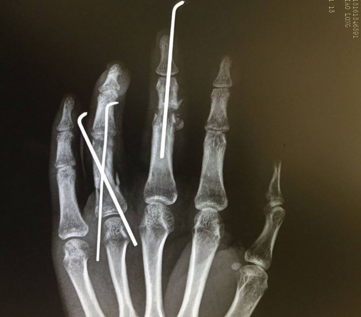

3.骨與關(guān)節(jié)的固定

整齊切傷的骨斷端一般縮短0.5cm,不整齊的損傷根據(jù)清創(chuàng)的情況給予相應(yīng)的骨斷端的切除。用直徑1mm的不銹鋼針1枚作髓腔內(nèi)固定,或用2枚不銹鋼針作交叉固定骨折,也有用微型螺絲固定或骨釘髓內(nèi)固定的方法。經(jīng)過關(guān)節(jié)的斷指,用2根相同粗細(xì)的克氏針作早期行關(guān)節(jié)融合術(shù)或掌指關(guān)節(jié)早期關(guān)節(jié)成形術(shù)。